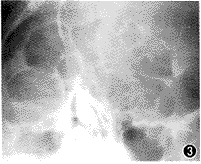

图3 X线片显示三眼眶